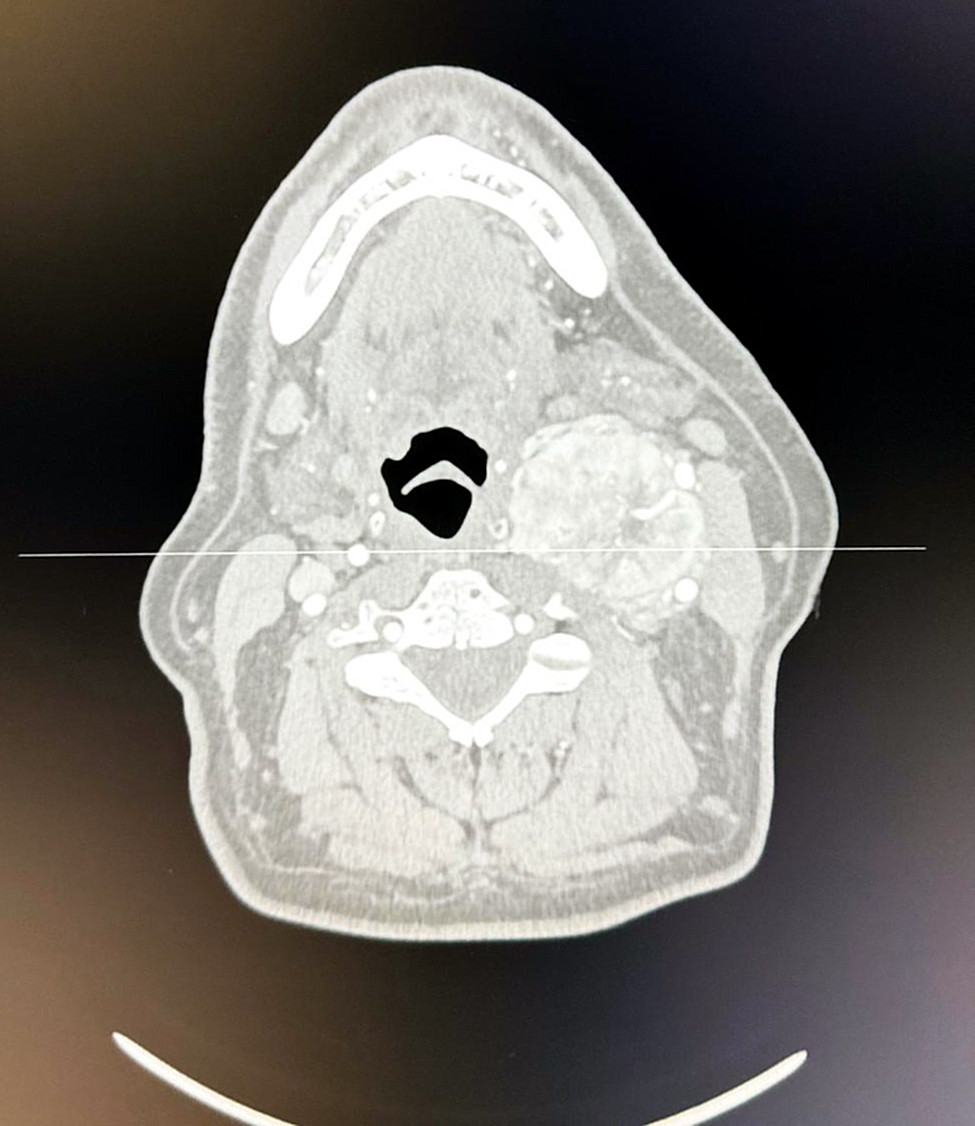

Un paciente de 55 años de edad fue sometido a un procedimiento quirúrgico en el servicio de Cirugía Vascular del Hospital Central, en donde le extrajeron un tumor denominado “Paraganglioma del Cuerpo Carotideo” también llamado PCC.

El Dr. Roberto Filizzola, jefe del servicio de Cirugía Vascular del Hospital Central señaló que “Primeramente, el paciente fue remitido a nuestra especialidad a través del servicio de Otorrinolaringología. El “Paraganglioma del Cuerpo Carotideo” contaba con 7 años de evolución, ya que es tumor que no produce dolor y es de lento crecimiento en la división de la arteria carótida del cuello”.

En la mayoría de los casos son benignos. Sin embargo, requieren de un diagnóstico y confirmación con estudios de imágenes y un tratamiento exhaustivo que generalmente implica la extirpación quirúrgica parcial o total.

Se procede a evaluar la extensión del tumor, su relación con las estructuras adyacentes, el suministro de sangre y de esa manera planificar la cirugía.